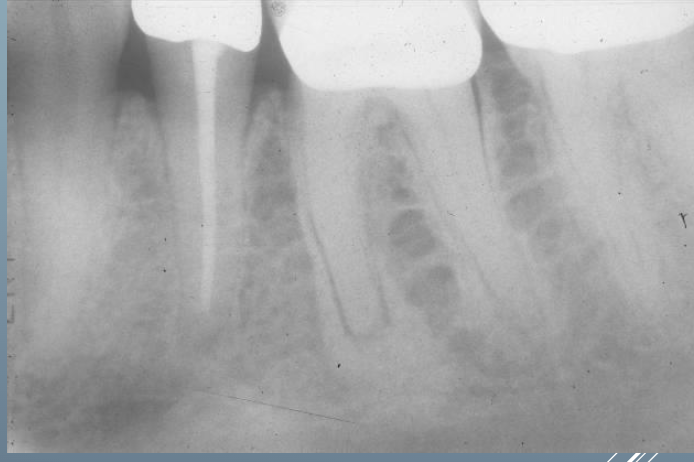

9

Q

What’s this?

A

HEMATOPOIETIC BONE MARROW DEFECT

FOCAL OSTEOPOROTIC BONE MARROW DEFECT